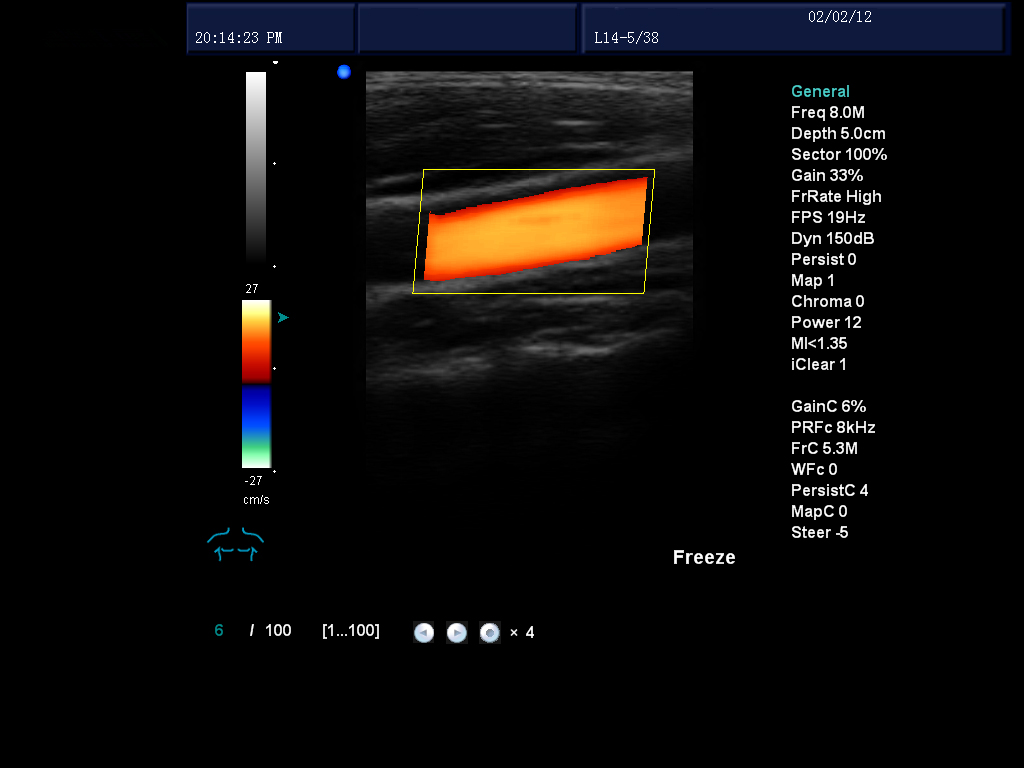

血流自動(dòng)跟蹤技術(shù):防止探頭移動(dòng)和病員呼吸所產(chǎn)生的血液噪音外溢,提高血流成像的空間分辨率。

動(dòng)態(tài)實(shí)時(shí)血管成像:通過精確的多普勒回聲信號(hào)自動(dòng)識(shí)別處理,減少血管壁和血流的多普勒信號(hào)回疊,使血管內(nèi)血液和血管多普勒成像顯示更清晰。